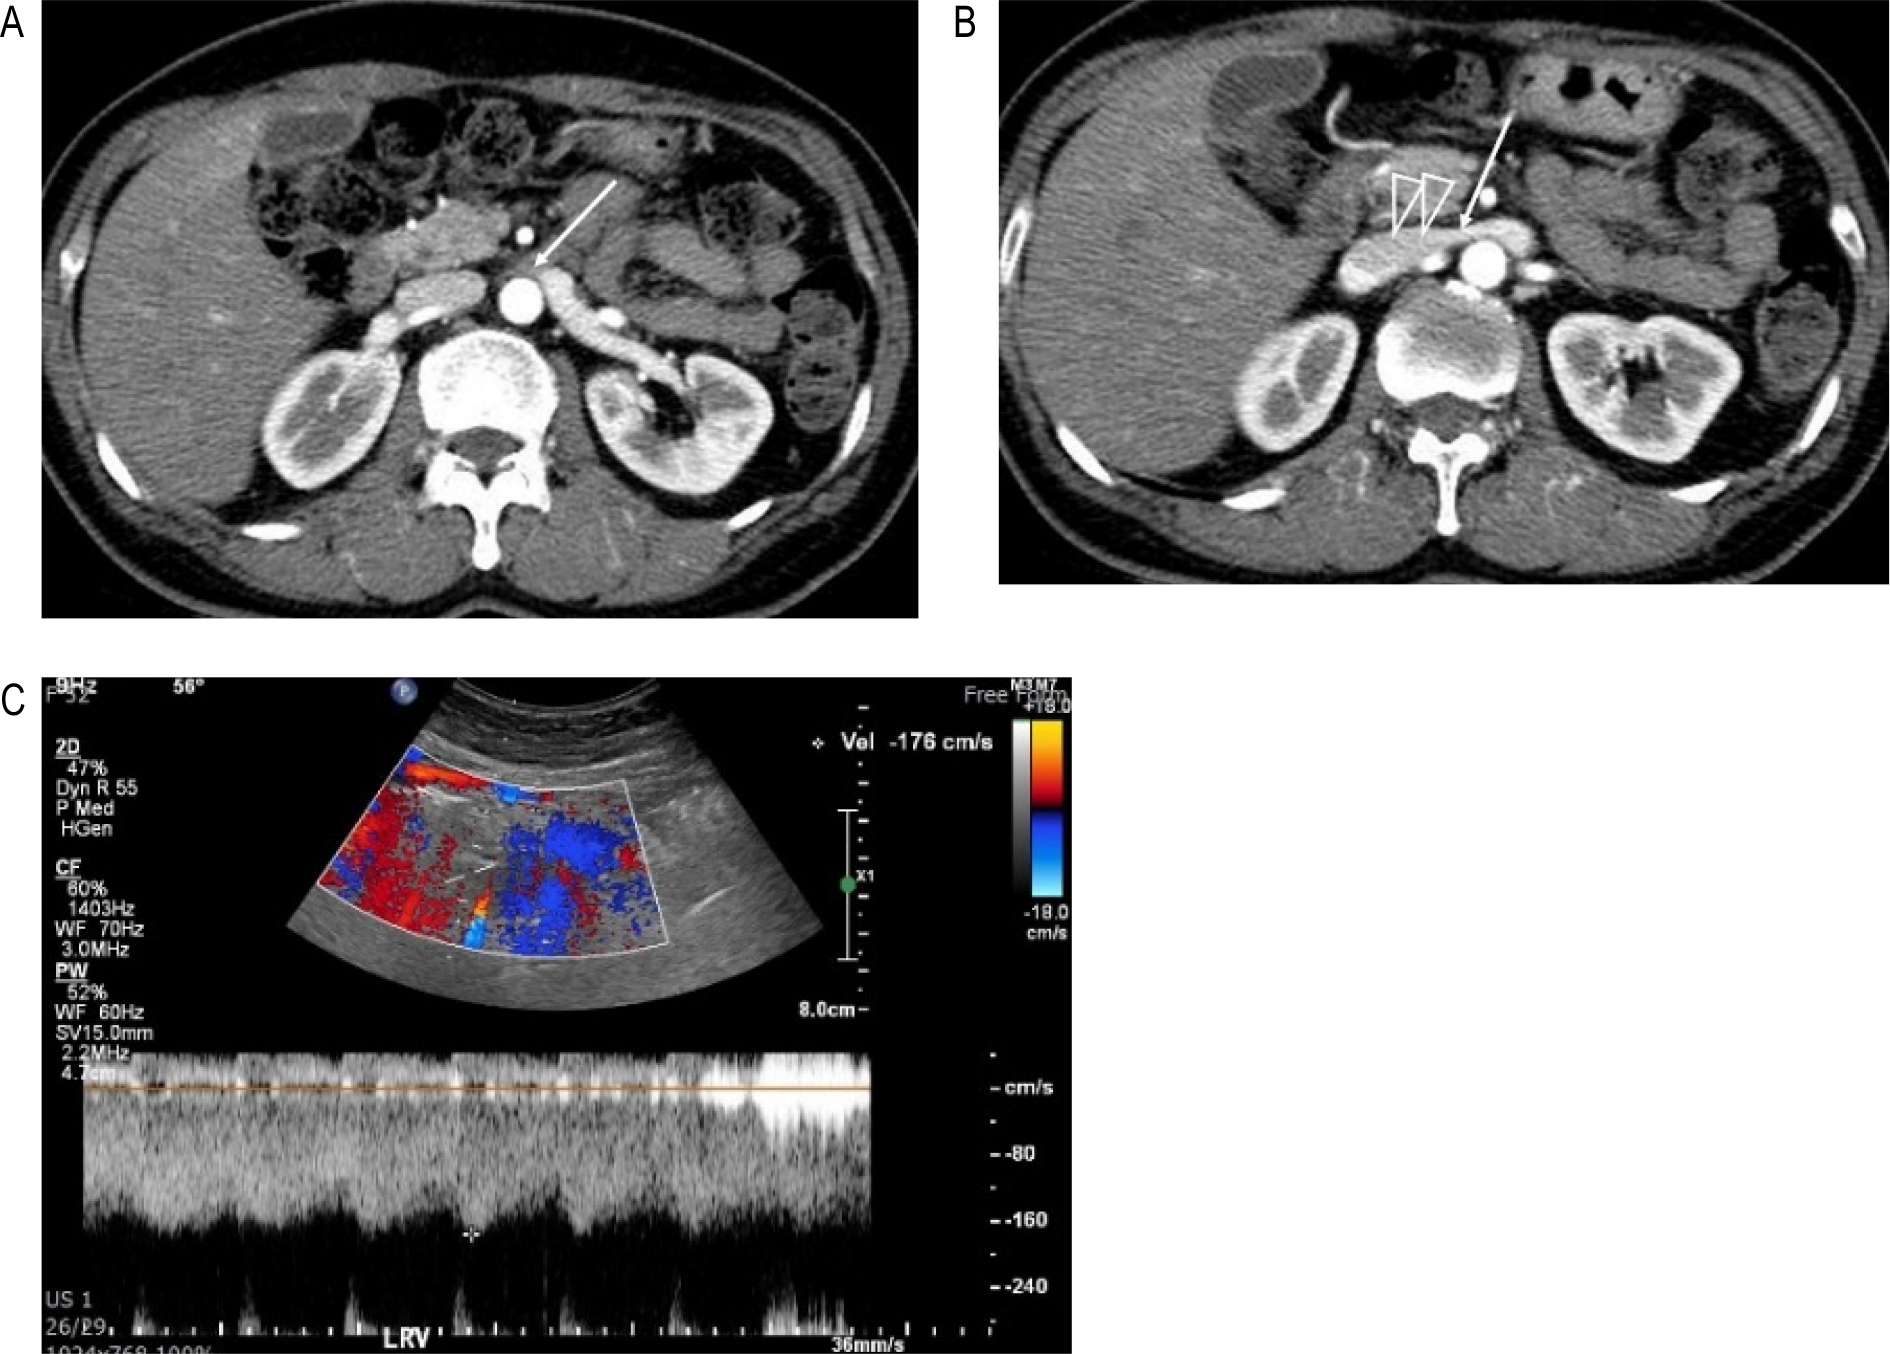

51세 여자로 지속적인 우상복부와 명치부위 통증이 있었다. 위내시경 검사에 이상소견 없었고 초음파 검사와 CT에 담낭결석이 발견되었지만 담낭벽은 두껍지 않았고 담낭 부위의 압통도 없어서 담낭결석이 원인은 아닌 것으로 생각 했었고 다른 이상소견도 발견하지 못했었다. 하지만 우상복부와 명치부위의 통증은 지속되어 담당을 제거하였으나 담낭제거 이후에도 같은 통증은 지속되었다. 당시의 CT를 다시 보았을 때 NCP가 의심되어서 [그림 4A,B] 도플러 검사를 했고 AM-LRV의 혈류속도는 176 cm/sec로 NCP가 확인되었다 [그림 4C]. 반듯이 누워 자던 평소의 수면자세를 교정한 후에 통증은 사라졌고 3년 정도 경과한 오늘까지 증상 없이 잘 지내고 있다.